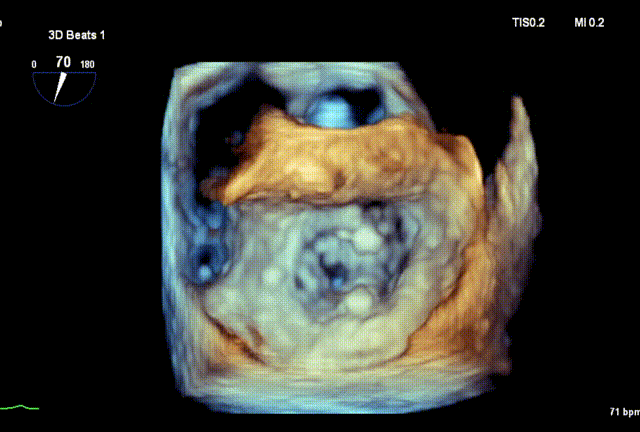

术前3D

DMR P2脱垂连枷(脱垂范围:12mm,连枷间距:3mm),反流2区,MR重度(VC:4* 10mm),A2:21mm,P2:10mm,AP:30mm,MVA约 4.7 cm²。